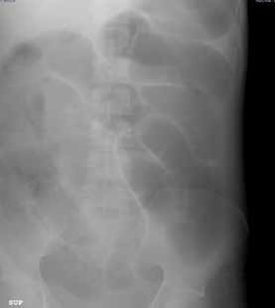

Entre sus exámenes de laboratorio se destacaba una hipopotasemia leve; en el estudio de radiología simple de abdomen, en bipedestación y posición supina, se observó un patrón de ‘pilas de monedas’ (figuras 1, 2, 3).